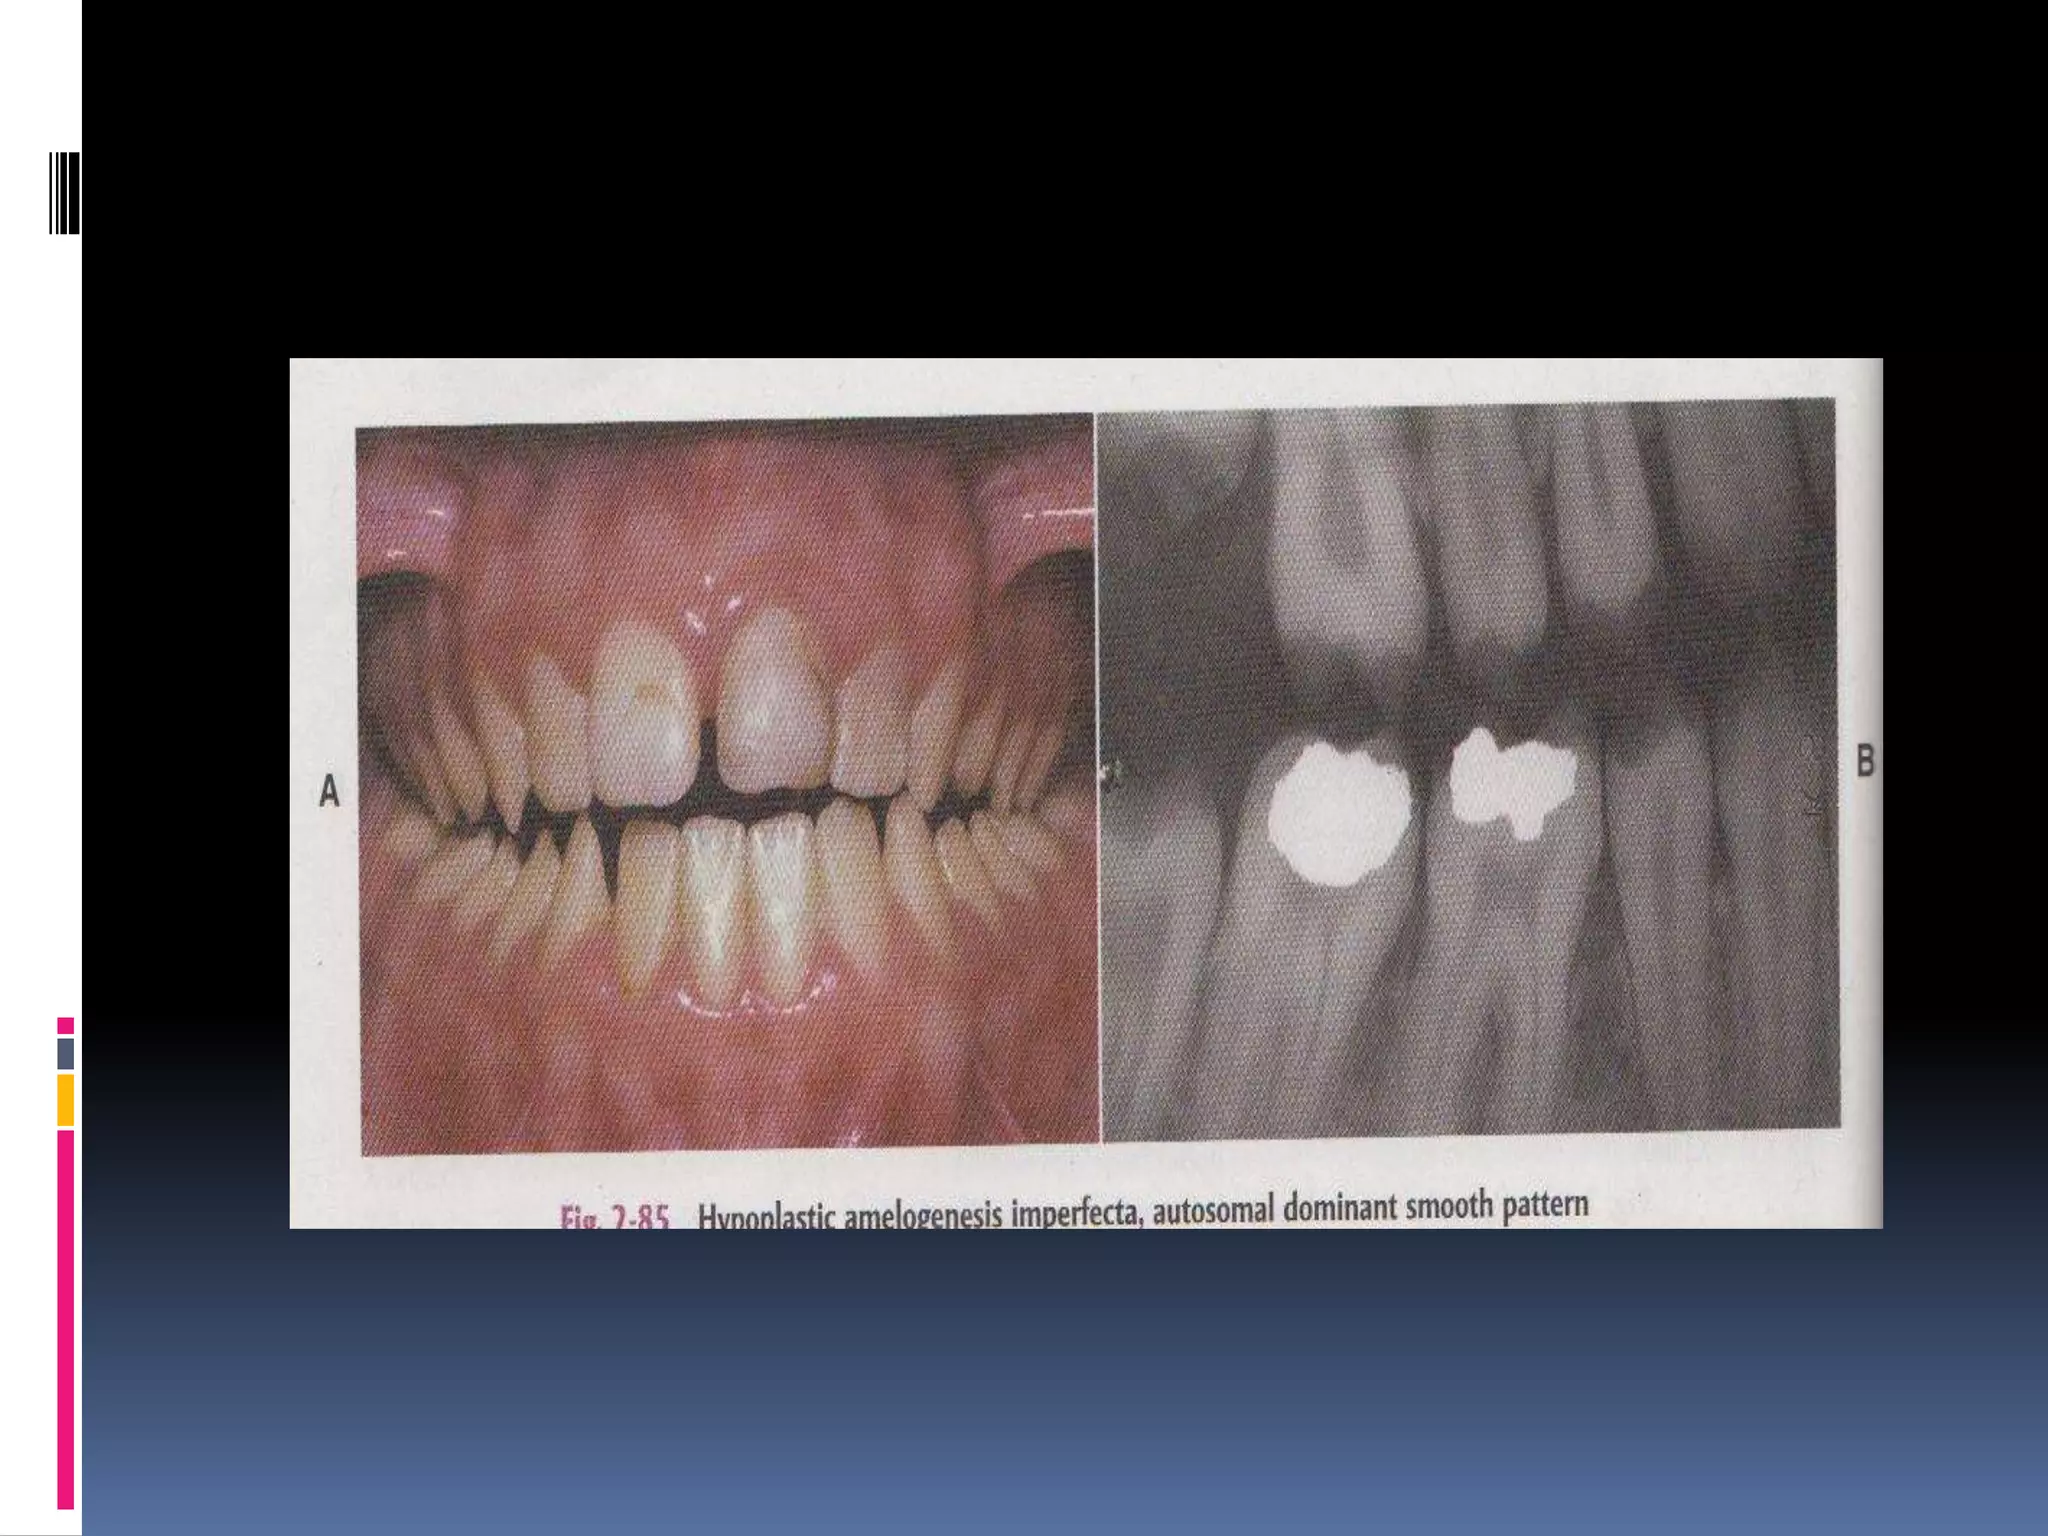

Autosomal dominant smooth pattern:

 Enamel is thin hard & glossy

 Open contact points

 Opaque white to translucent brown.

radiology

 Hypoplastic - tapered crown

 lack of contact